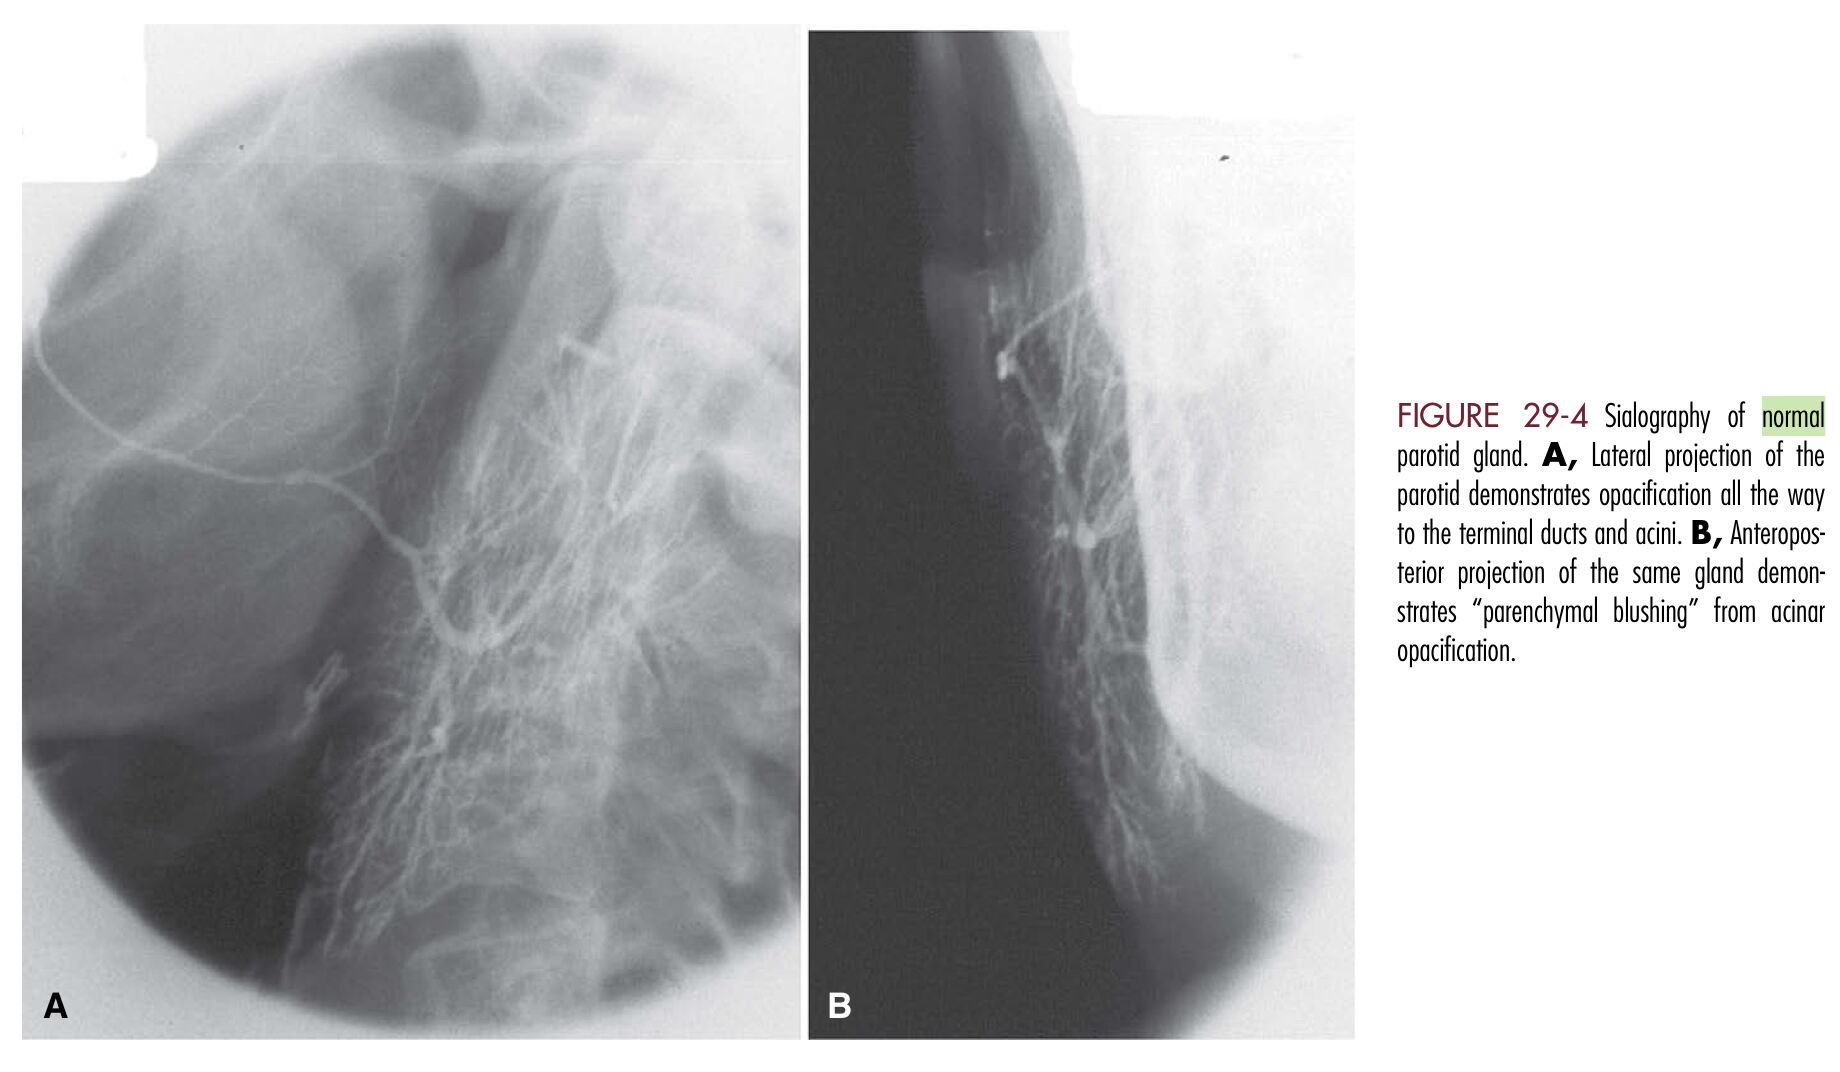

70.下列那一唾液腺攝影圖像可以診斷為涎腺管炎(sialodochitis) ?

(A)修格連氏症候群

(C)(D)為

正常

腮腺影像